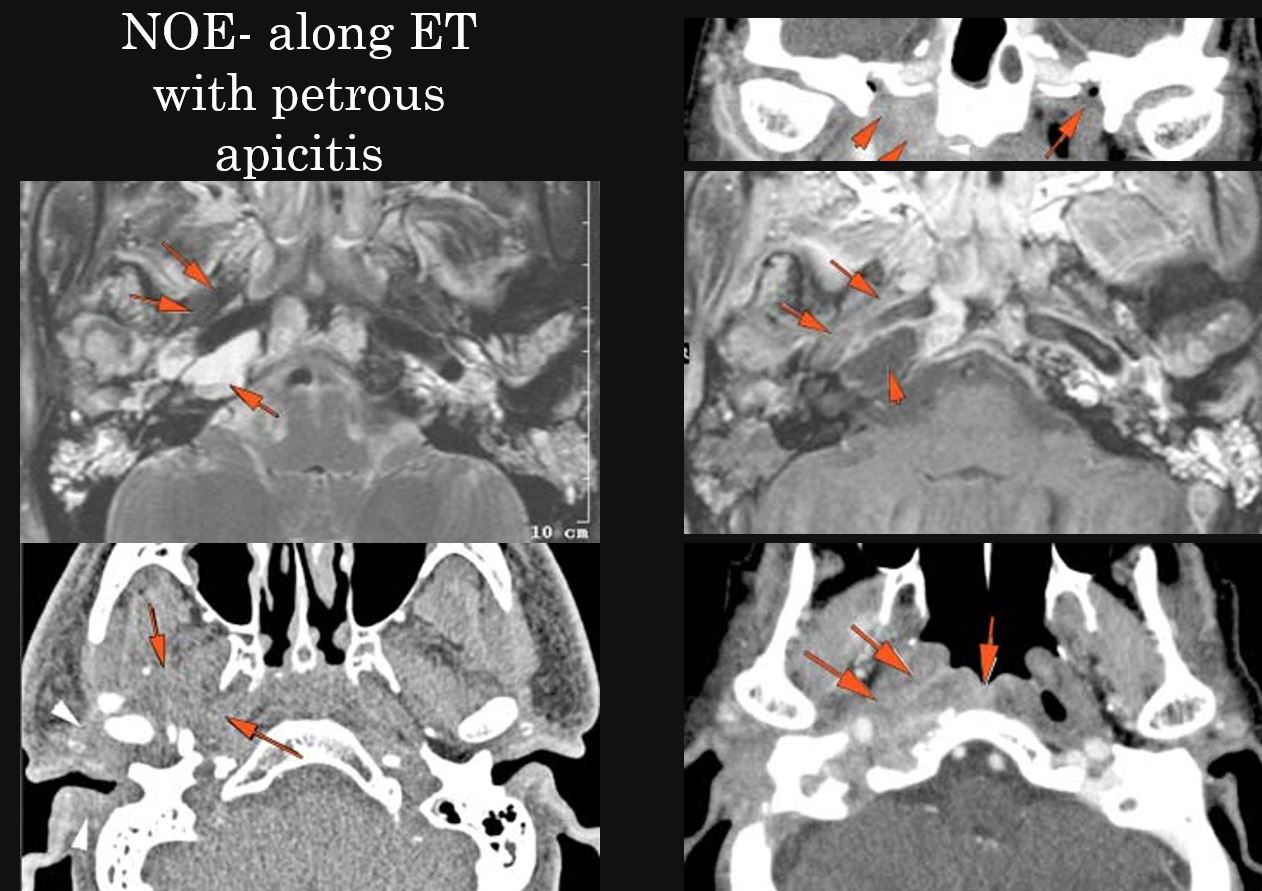

There is an erosive process, subperiosteal or otherwise spreading along the anterior-inferior aspect (extracranial aspect) of the petrous apex involving the bony Eustachian tube and/or carotid canal. [Yes/No]

The petrous apex is abnormal. [Yes/No]

Petrous apicitis associated with middle ear and mastoid disease.

Petrous apicitis with an etiology other than associated with middle ear and mastoid disease.